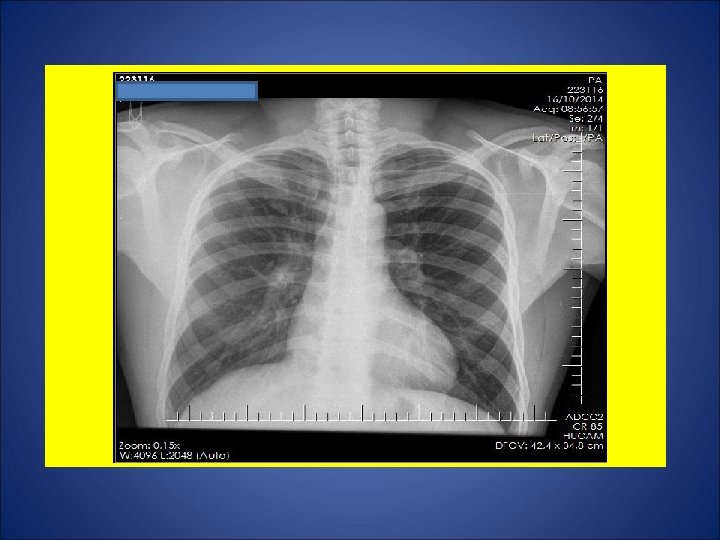

CASO 4, masculino, 30 anos, natural de Vitoria (ES), residente na Serra (ES), pedreiro. Há 2 meses e meio, tosse não produtiva, sudorese noturna, calafrios, adinamia. Surgimento de febre 20 dias e de expectoração purulenta 15 dias após. Episódios de escarros hemoptóicos 10 dias atrás e em 18 Out. Há 1 mês, dor em hemitórax esquerdo agravada com a tosse. Há 20 dias, dispnéia aos médios esforços. Durante os últimos 15 dias, perda de 10 Kg. Negou contato com casos de tuberculose. Negou tuberculose prévia. Negou tabagismo e etilismo. HIV negativo. Ex. fisico: P=73 Kg, Altura= 1, 63 m, IMC= 27, 5 Kg/m 2 (discreto sobrepeso), FC = 110 bpm. Marca de BCG em MSD.

ESCARROS ESPONT NEOS: 1º) 20/10/14: 10 m. L – PURULENTO - 30 min: BAC NEG - TRM: M. tuberculosis NÃO DETECTADO – CULT em curso 2º) 20/10/14: 10 m. L – MUCOPURULENTO – 30 min: BAC NEG – CULT em curso 3º) 21/10/14: 10 m. L – MUCÓIDE – 30 min: BAC NEG – CULT em curso